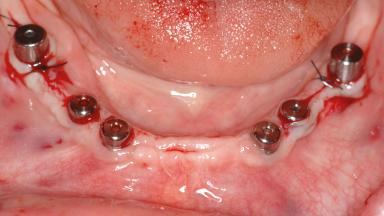

Le Fort I Interpositional Graft and Mandibular Sandwich Osteotomy for Maxillofacial Rehabilitation after Severe Periodontitis

A 47-year-old woman who had suffered from aggressive periodontitis requiring a number of periodontal interventions over more than 10 years was referred by her general dental practitioner and periodontologist for bone augmentation and implant therapy. Her failing dentition had already been scheduled for extraction. The patient expressed a desire for implant-supported fixed restorations and esthetic improvement of her lower face. She had agreed to consult with a maxillofacial surgeon after the referring dentist had suggested bone augmentation. An initial examination by the maxillofacial surgeon revealed mobility of all residual teeth in a patient who was very unhappy with the function of her removable partial dentures. Due to periodontally migrated flaring teeth and loss of occlusal support, the vertical dimension of occlusion was dramatically reduced. The patient was displeased with her lower face because of deepened nasolabial, commissural, and supramental folds.

# of Implants 14

Type of Implants Two-Piece

Bone Augmentation Horizontal|Sinus Floor Elevation|Staged|Vertical

SAC Level Complex

Defining Characteristics Fully edentulous upper jaw to be rehabilitated with four or more implants

Modality Fixed hybrid bridge on 5+ implants